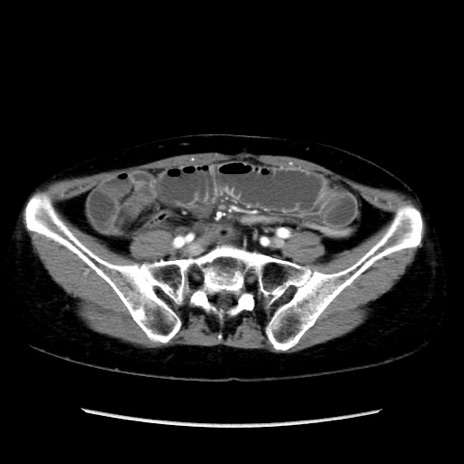

症例32(横断像)

【症例】40歳代 女性

【主訴】上腹部痛、嘔気・嘔吐

【現病歴】約9時間前頃から急に上腹部痛、嘔気、嘔吐が出現。改善しないため救急要請。

【既往歴】子宮頚癌(広汎子宮全摘術、放射線療法)、腸閉塞

【身体所見】腹部:平坦、軟、腸雑音亢進、上腹部を中心に腹部全体に圧痛あり。

【データ】WBC 8400、CRP 0.03